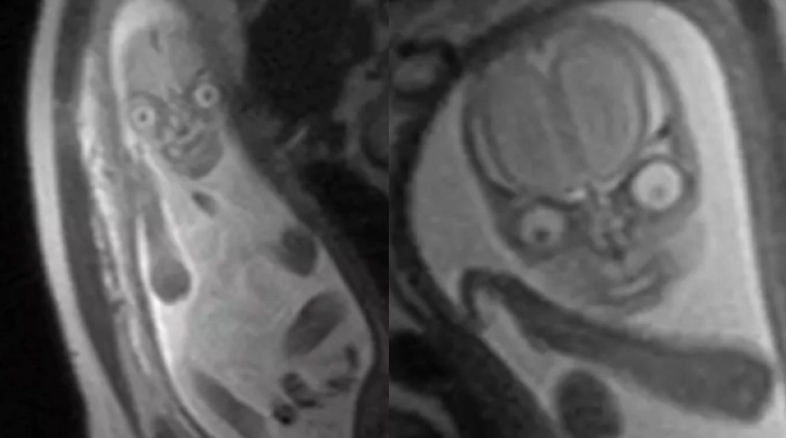

Ωστόσο, αν κάνετε ποτέ μια μαγνητική τομογραφία του μελλοντικού παιδιού σας και μοιάζει με” δαίμονα”, σχεδόν σίγουρα δεν θα αφήσετε ποτέ αυτές τις εικόνες να δουν το φως της δημοσιότητας. Κάτι παρόμοιο συνέβη και τα social media παρατήρησαν το ίδιο. Κοίτα.

Οι εικόνες που έχουν κάνει το γύρο του διαδικτύου φαίνεται να προκαλούν ανησυχία, αφού φαίνεται να έχουν ληφθεί από ένα πλάσμα εξωπραγματικό. Εικόνες σαν αυτές γίνονται συχνά δημοφιλείς στα μέσα κοινωνικής δικτύωσης, επειδή οι άνθρωποι σοκάρονται που ένα νεογέννητο μπορεί να μοιάζει έτσι.

The real reason they discourage MRIs during pregnancy is because then people would realise they’re incubating nightmare demons and would be rightfully terrified pic.twitter.com/55zEeOofsP

— Katie (@ZiziFothSi) May 19, 2021

Σε ό,τι αφορά τις φωτογραφίες από τη μαγνητική αυτού του μωρού, ήταν τόσο παράλογες που το Snopes, ένας ιστότοπος ελέγχου γεγονότων, ερεύνησε αν ήταν αληθινές. Κατέληξαν στο συμπέρασμα ότι οι εικόνες ήταν σχεδόν σίγουρα ακριβείς, και μίλησαν ακόμη και με έναν μεταπτυχιακό βοηθό ερευνητή και υποψήφιο διδάκτορα στο Πανεπιστήμιο του Ουισκόνσιν.

Ο Jason Moody μελετά τις αλλαγές του εγκεφάλου που σχετίζονται με την ηλικία χρησιμοποιώντας τεχνολογία μαγνητικής τομογραφίας και είπε στον ιστότοπο ότι αυτές οι τρομακτικές εικόνες δείχνουν τι είναι ικανές αυτές οι τεχνολογίες.

“Η μαγνητική τομογραφία καθιστά πολύ εύκολη τη διαφοροποίηση μεταξύ των διαφορετικών τύπων μαλακών ιστών που βρίσκονται στο σώμα και εμείς είμαστε ως επί το πλείστον μαλακοί ιστοί. Θυμηθείτε ότι είμαστε κυρίως νερό”, είπε ο Moody.

Προσθέτοντας, «Ένα από τα κύρια χαρακτηριστικά αυτών των εικόνων είναι οι σημαντικές διαφορές μεταξύ των ματιών, του εγκεφάλου, της μύτης και του υπόλοιπου προσώπου».